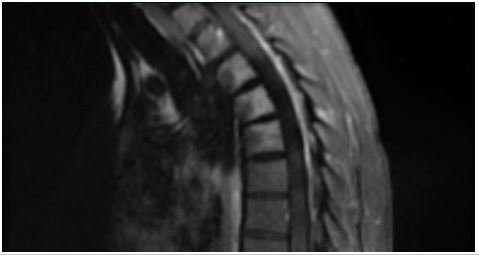

Her initial lab work was unremarkable with the exception of mild hypoglycemia of 63mg/dL, CRP was mildly elevated at 0.60mg/dL with a normal ESR. An MRI of the cervical, thoracic, and lumbar spine revealed a short segment enhancing cord abnormality which was located at the T3-T4 level involving most of the spinal cord. There was minimal disc bulging at the levels of L3-L4, L4-L5, L5-S1 without significant spinal canal stenosis or neural foraminal narrowing. No evidence of spinal cord infarction was observed (Figure 1-3). She was tested for COVID-19 given neurologic manifestations of COVID-19 which was positive. She was admitted to the hospital for workup and management of her symptoms under the Department of Internal Medicine with Neurology consultation.

Figure 3: T2 sequence from thoracic MRI performed 10 days following initial MRI in Figure 1 redemonstrating myelitis at the level of T3-T4.